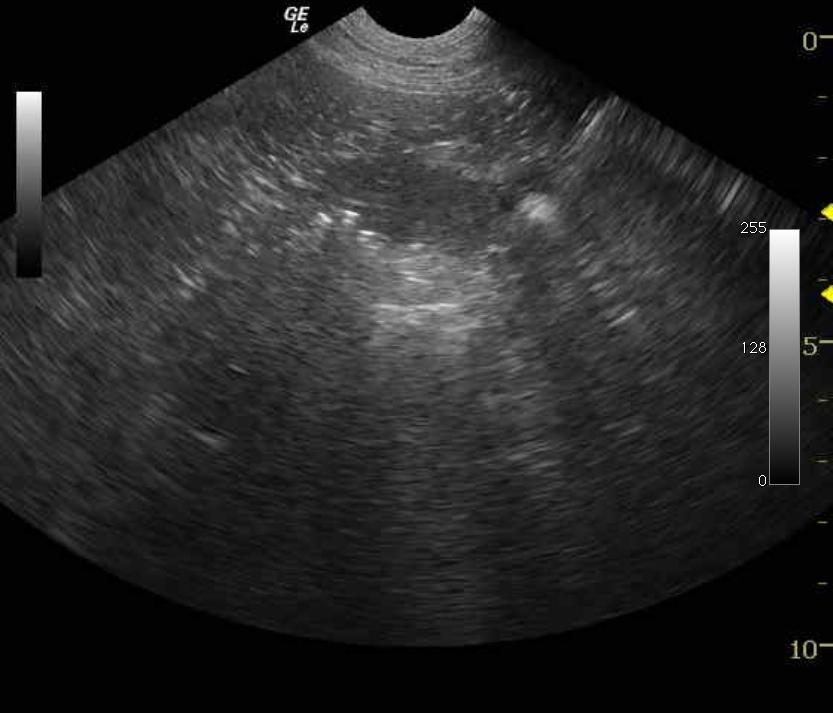

The gastrointestinal tract revealed a significant dilation of the stomach and distal small intestine with fluid material. Small intestinal obstructive material was noted measuring approximately 3.5 cm with areas of adhesion in the region caudal to the spleen. The presence of empty small intestine with dilated small intestine in the same view comprises an obstructive pattern.

Small intestinal obstructive pattern, probable foreign body, stricture, or focally compromised intestine